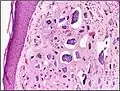

| Micrograph of calcinosis cutis. The calcification is purple (bottom of image). H&E stain. | |

Histopathology of calcinosis cutis in human tissue

Histopathology of calcinosis cutis in human tissue